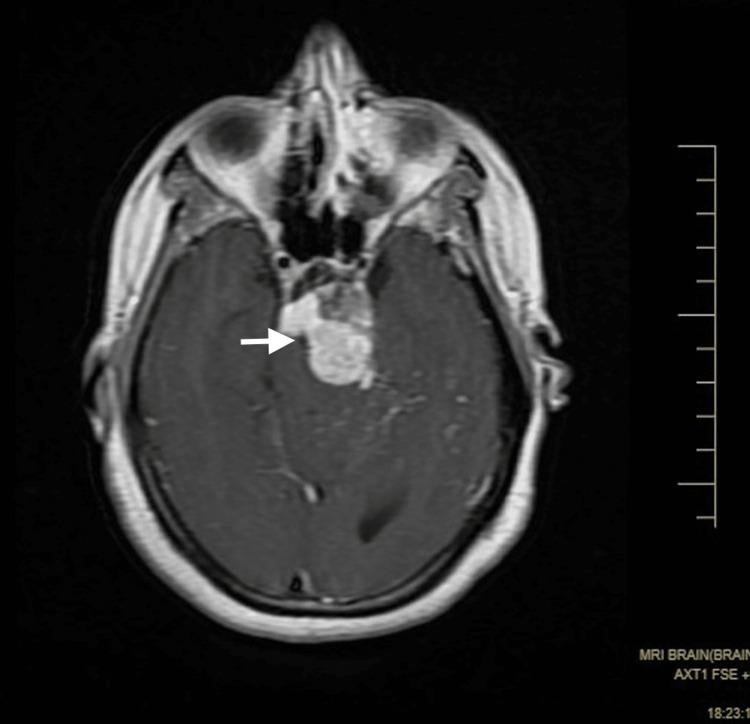

Magnetic Resonance Imaging Findings in a Rare Case of a Ruptured Intracranial Dermoid Cyst.

Intracranial dermoid cysts are rare, benign, congenital, and slow-growing cystic lesions. They contain mature squamous epithelium, apocrine, eccrine, sebaceous glands, and ectodermal structures. The rupture of intracranial dermoid cysts is a rare event and can cause life-threatening conditions.

颅内皮样囊肿是罕见的、良性的、先天性的、生长缓慢的囊性病变。它们包含成熟的鳞状上皮、顶泌汗腺、小汗腺、皮脂腺和外胚层结构。颅内皮样囊肿破裂是罕见事件,可导致危及生命的情况。